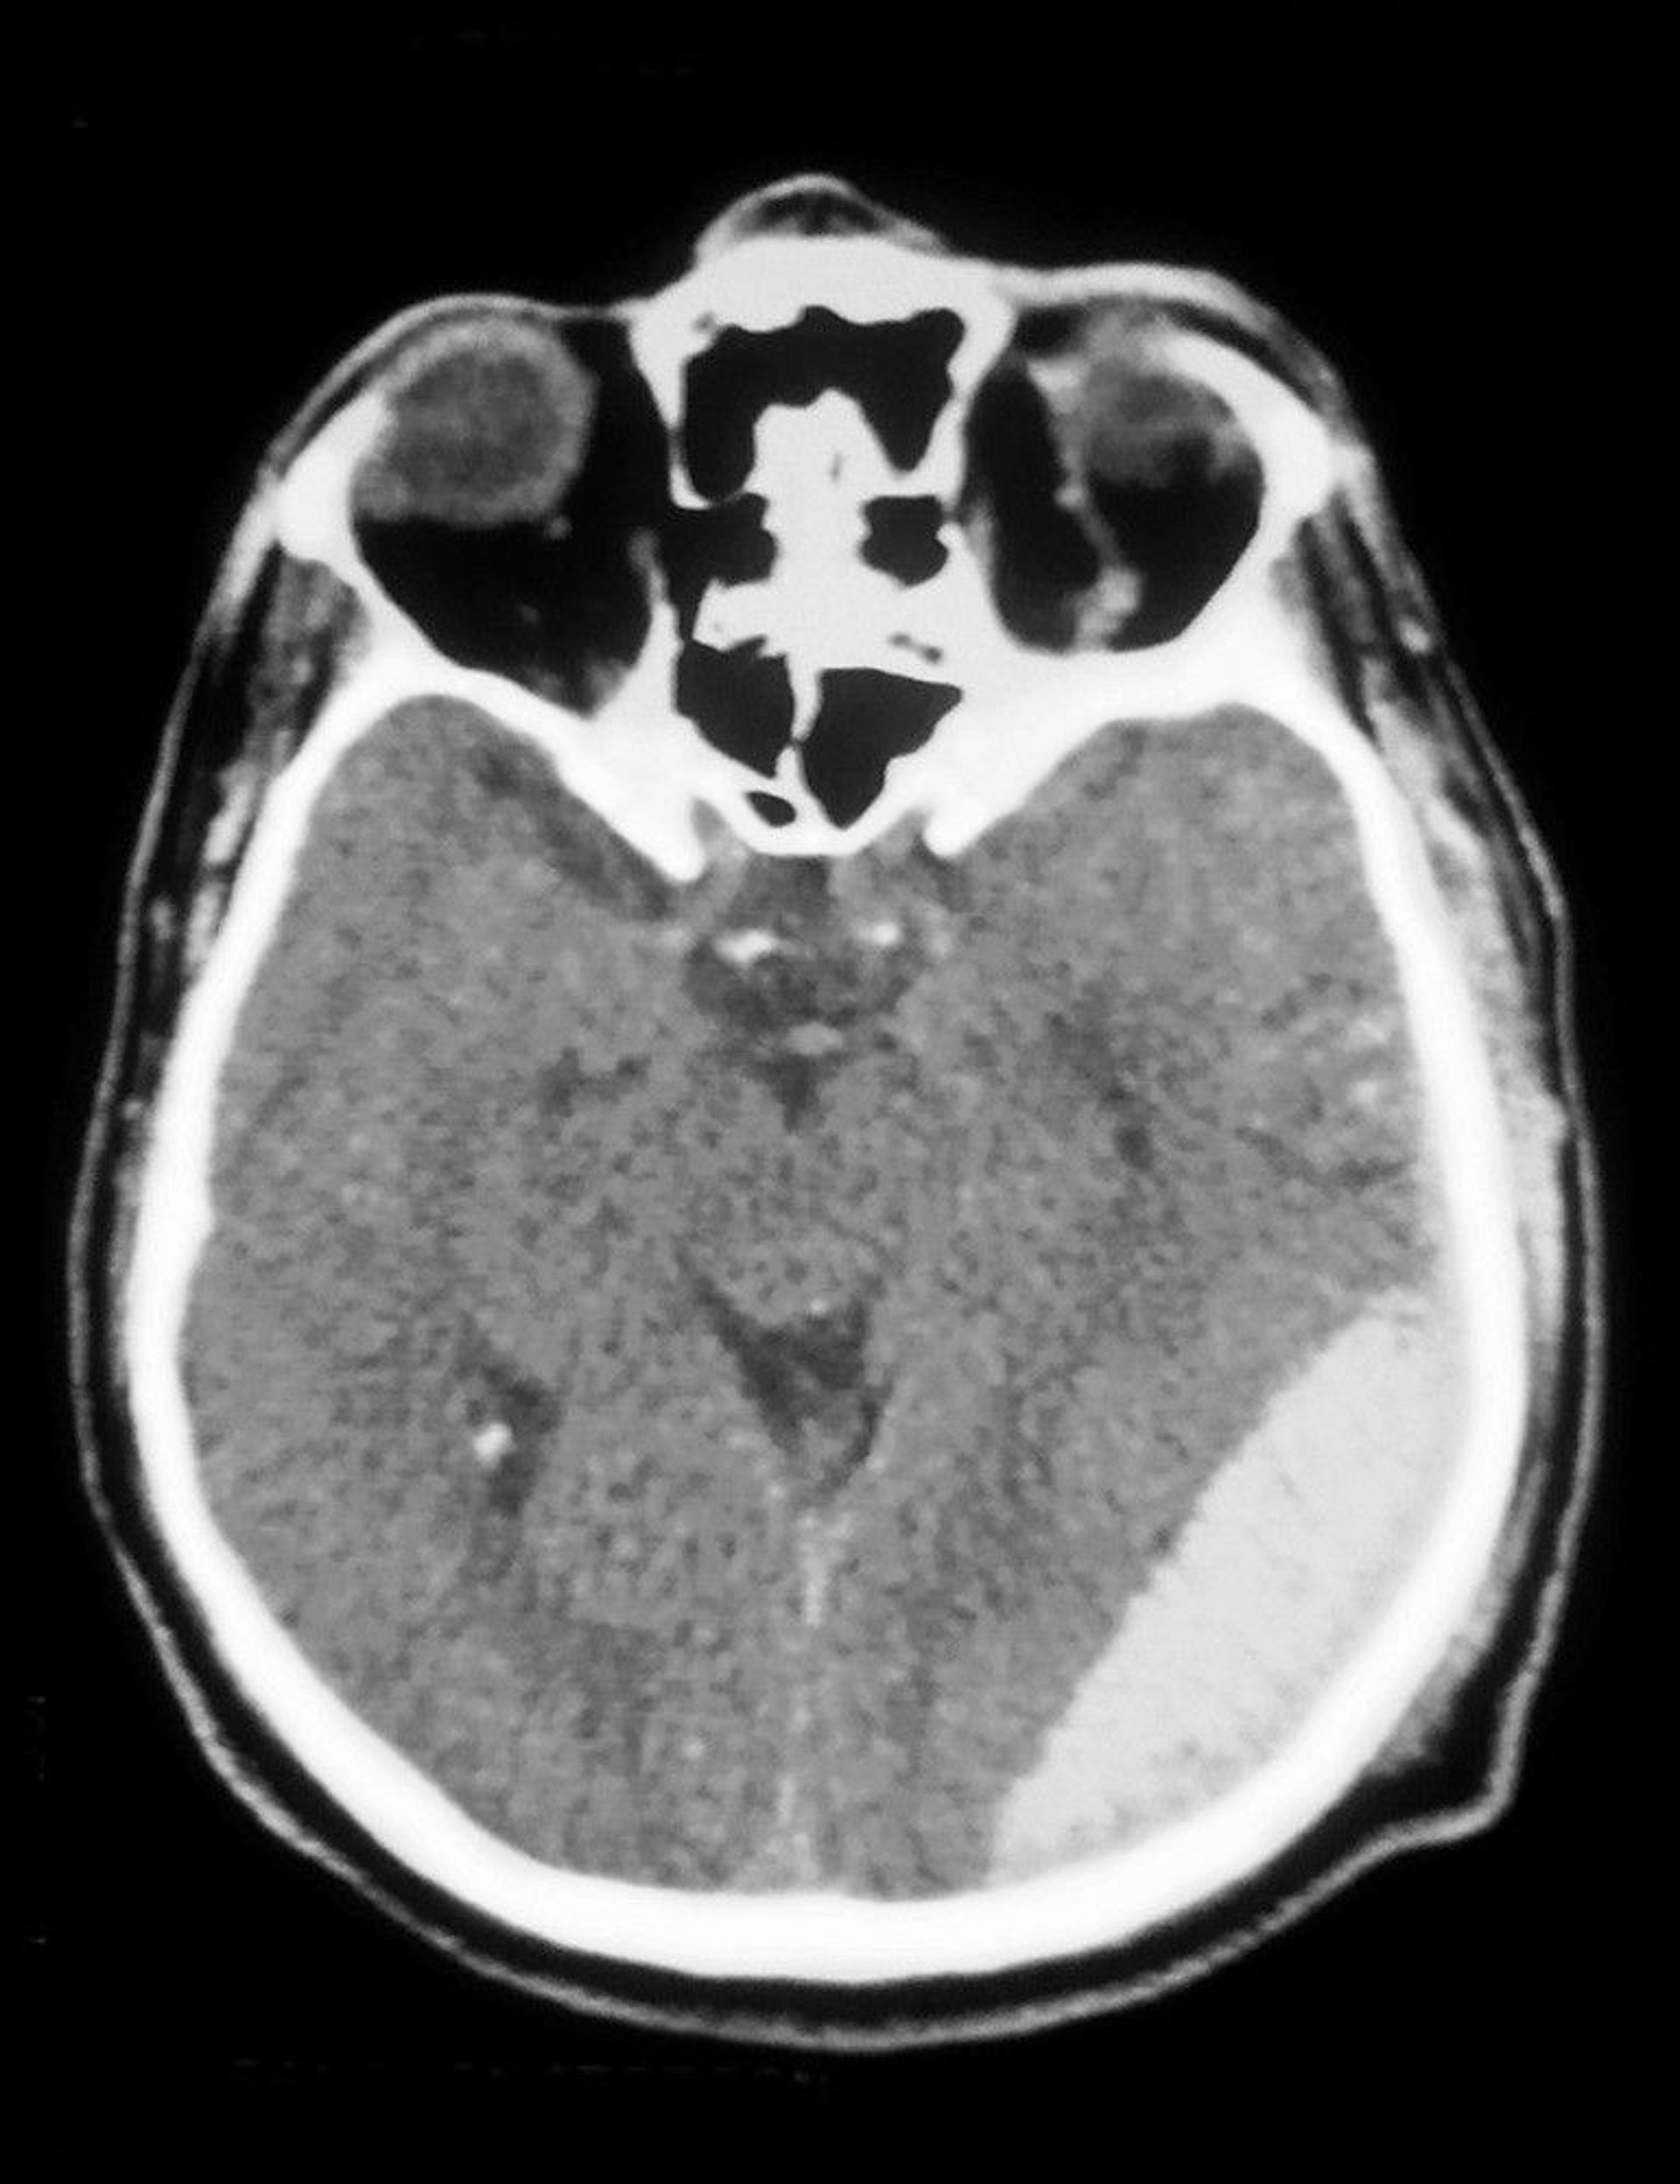

CT scan shows an epidural hematoma (opacity at bottom right).

Cavallini James/BSIP/SCIENCE PHOTO LIBRARY